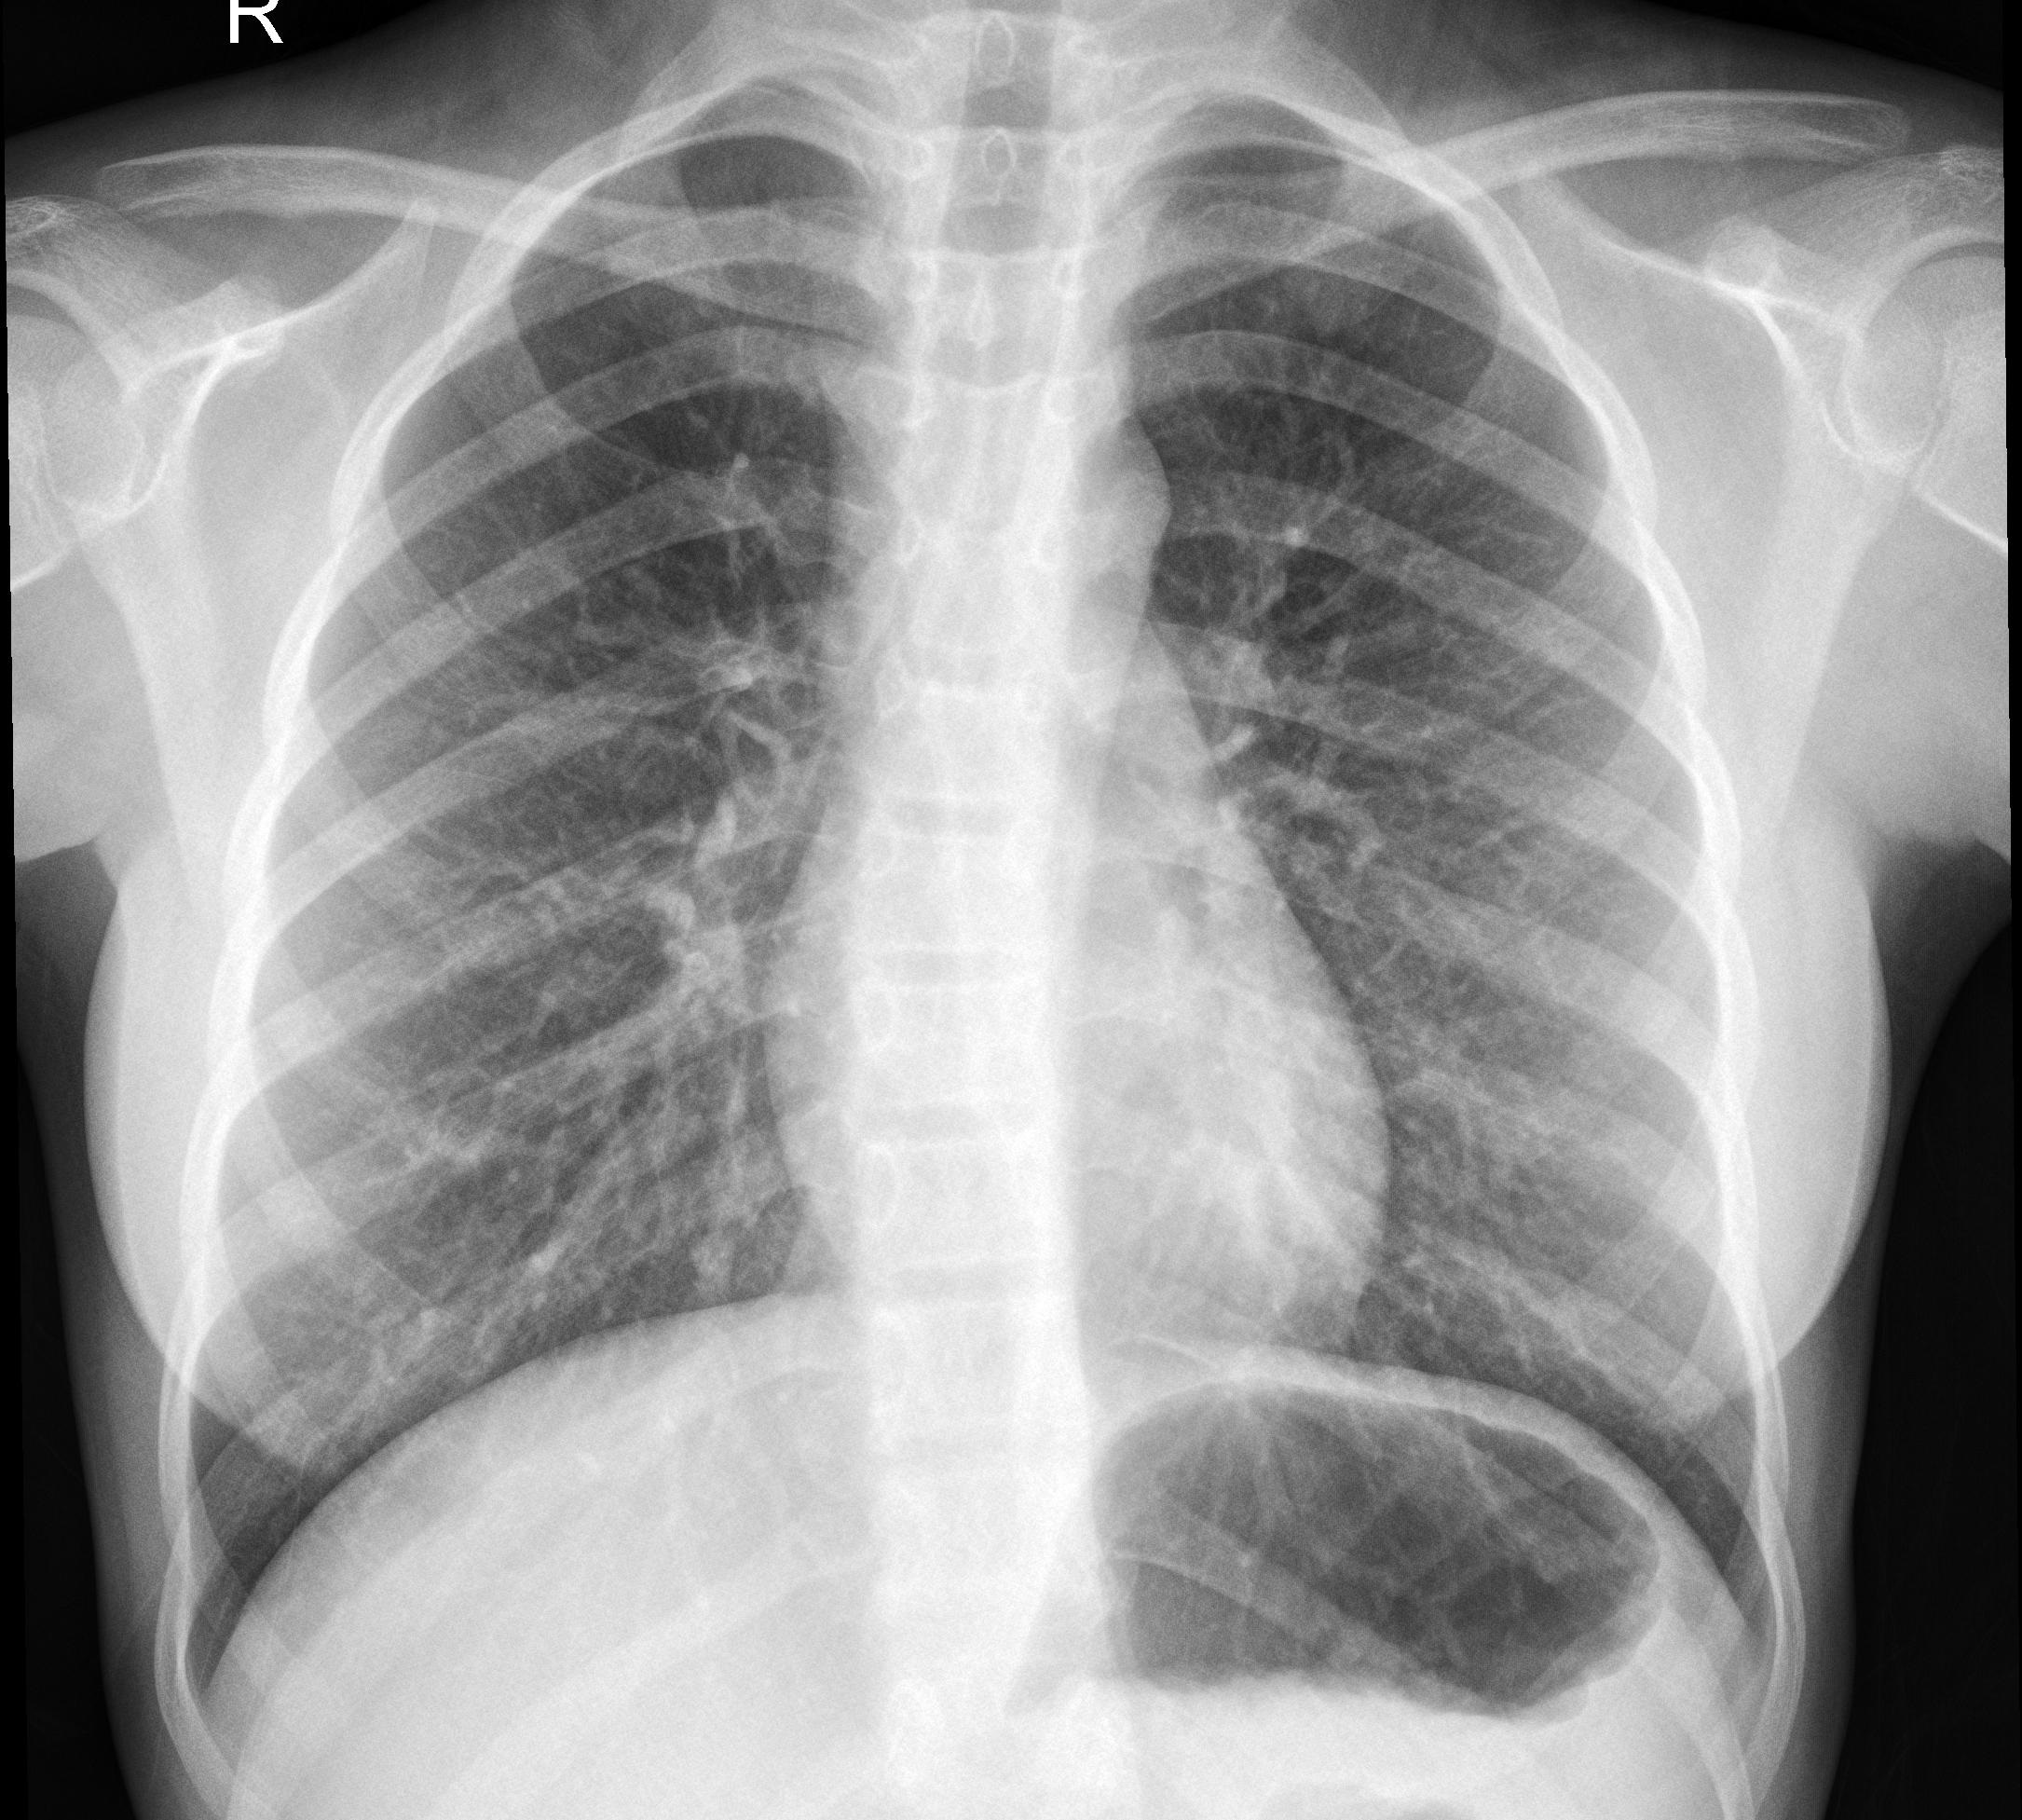

Die Verbreitung der Coronavirus-Erkrankung schritt so schnell voran, dass sie Krankenhäuser in der Diagnose nicht hinterher kamen.Aus diesem Grund wurde die schnelle Produktion der RT-PCR Test-kits von großer Bedeutung und ging in Massenproduktion, was jedoch auch einige Probleme nach sich zog u.a verminderte Genauigkeit und die Unzuverlässigkeit einiger Kits. Studien über die Symptome des Virus ermöglichten eine Kategorisierung der Infizierten. Als Hauptsymptome gelten Fieber und Atembeschwerde bzw. hohes Fieber und Atemstörung als Symptome der Schwererkrankten. Ausgeführte Studie haben gezeigt, dass in den ersten Phasen der Krankheit, Röntgenbilder der Brust ein genaueres Ergebnis liefern als die ältere Methode der Test-Kits. Für diesen Zweck haben wir eine App erstellt, welche durch die Analyse der Röntgenbilder die Krankheit und Ihre unterschiedlichen Phasen präziser erkennbar macht.

Beispielbilder von Menschen mit Corona

Bild 1